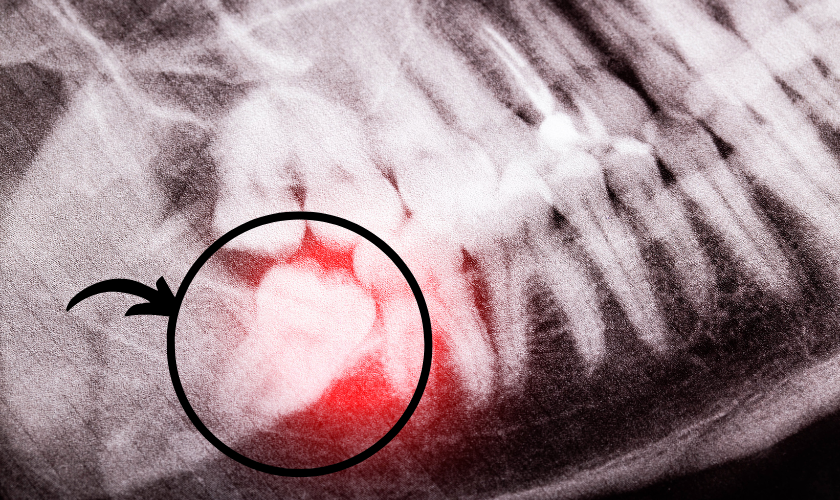

Impacted wisdom teeth, which are unable to erupt due to obstruction by other teeth or jawbone fully, often require surgical extraction. The degree of impaction, whether the tooth is partially or fully impacted, can influence the complexity of the procedure and, consequently, the cost. Fully impacted teeth, which are completely covered by gum tissue or jawbone, generally necessitate more intricate surgical techniques, potentially increasing the cost.